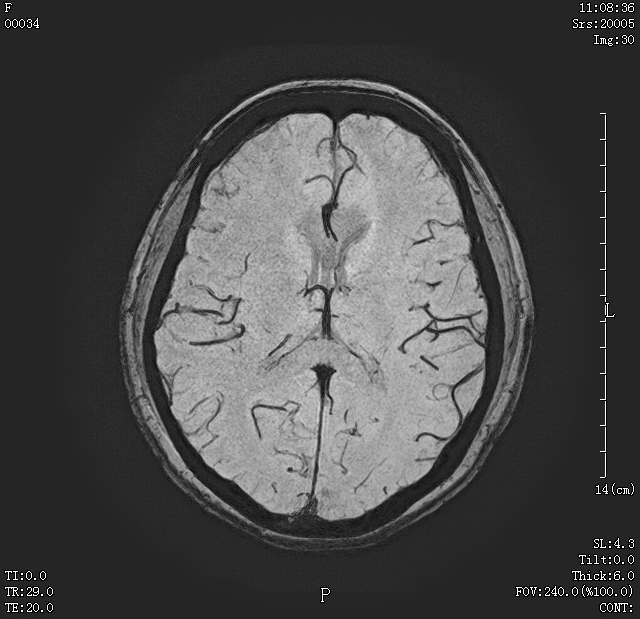

07 颅脑磁敏感加权成像(SWI) 可发现颅内微小出血灶;静脉畸形等;可发现高血压及外伤后患者的微小出血灶。